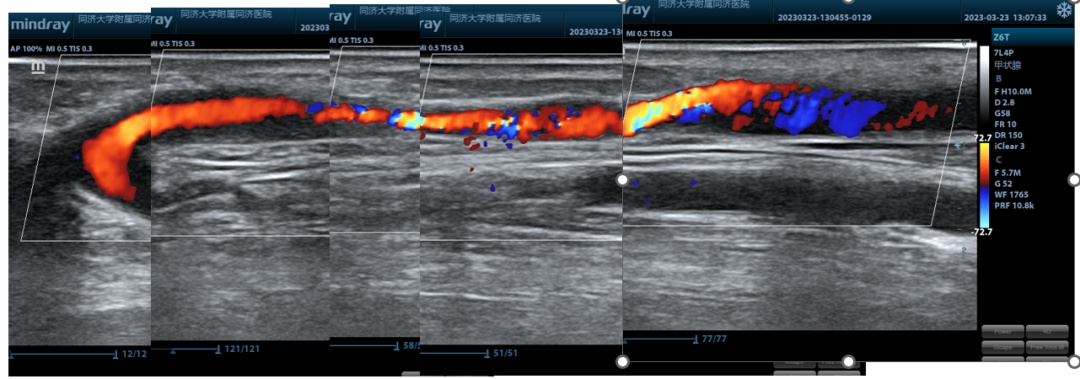

术前超声检查—AVF全程图

3年前,76岁的武先生因为肾功能衰竭开始使用自体动静脉内瘘作为血管通路,进行血液透析治疗。近1年来,因内瘘狭窄导致血流量不足无法血液透析,曾行两次介入下内瘘球囊扩张术,但最近一次仅仅维持了3个月就再次复发。最近武先生再次出现内瘘血流量下降,无法维持正常透析,于是他找到同济大学附属同济医院肾脏内科血管通路组进行评估,超声检查内瘘血管内可见头静脉长段狭窄伴内膜增生明显,狭窄段血管管腔内径不足2mm。